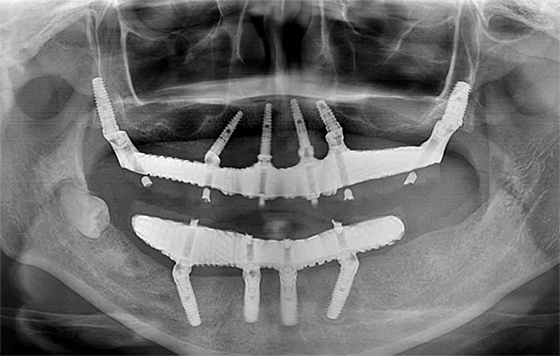

レントゲンを撮ると、ほとんどの歯が重度の歯周病で保存できない状態となってしまっていたので、抜歯して上下の顎をオールオン4で再建しました。

この患者様は、骨が極端に少ないため、あらかじめ患者様の顎骨を再現した模型上でシミュレーション手術を3回行い、ベストな位置にインプラントを埋め込むことができました。

この患者様の場合、治療後半年後のレントゲン写真を見ると、骨とインプラントがしっかりと結合している様子が確認できたので、最終的な人工歯を装着しました。